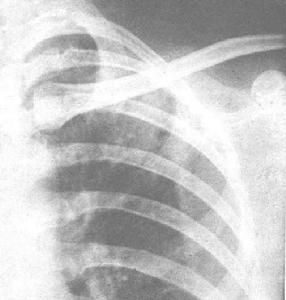

結核病分原發和繼發性,初染時多為原發(Ⅰ型);而原發性感染後遺留的病兆,在人抵抗力下降時,可能重新感染,通過血循環播散或直接蔓延而致繼發感染(Ⅱ型~Ⅳ型)。1、原發性肺結核(Ⅰ型):常見於小兒,多無症狀,有時表現為低熱、輕咳、出汗、心跳快、食慾差等;少數有呼吸音減弱,偶可聞及乾性或濕性羅音。